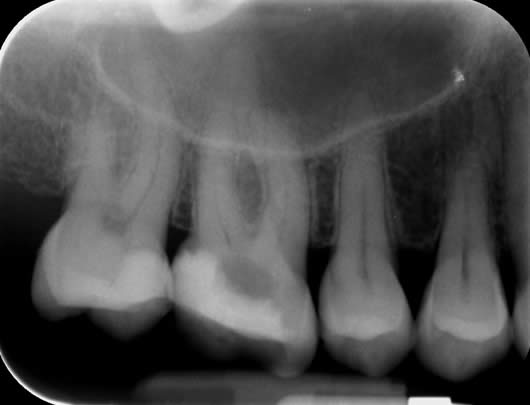

Case 6: Root canal treatment- additional roots.

Occasionally, some teeth can have additional roots. This case shows a lower molar tooth with an addition root. These lower molars normally have two roots with 3-4 canals. This tooth had 3 roots with 5 canals.

Before treatment LL6

Following root canal treatment LL6 (normally this tooth only has two roots)